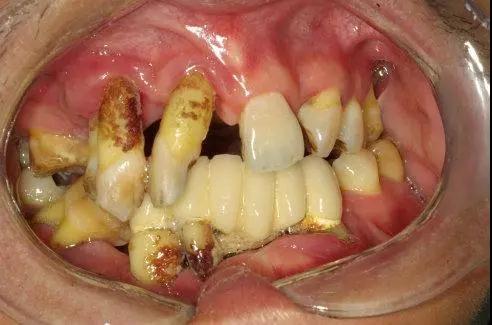

国人口腔环境触目惊心!

不良后果

咀嚼困难、食物嵌塞、邻牙倾斜

对牙合牙伸长、咬合紊乱

牙周病

龋病